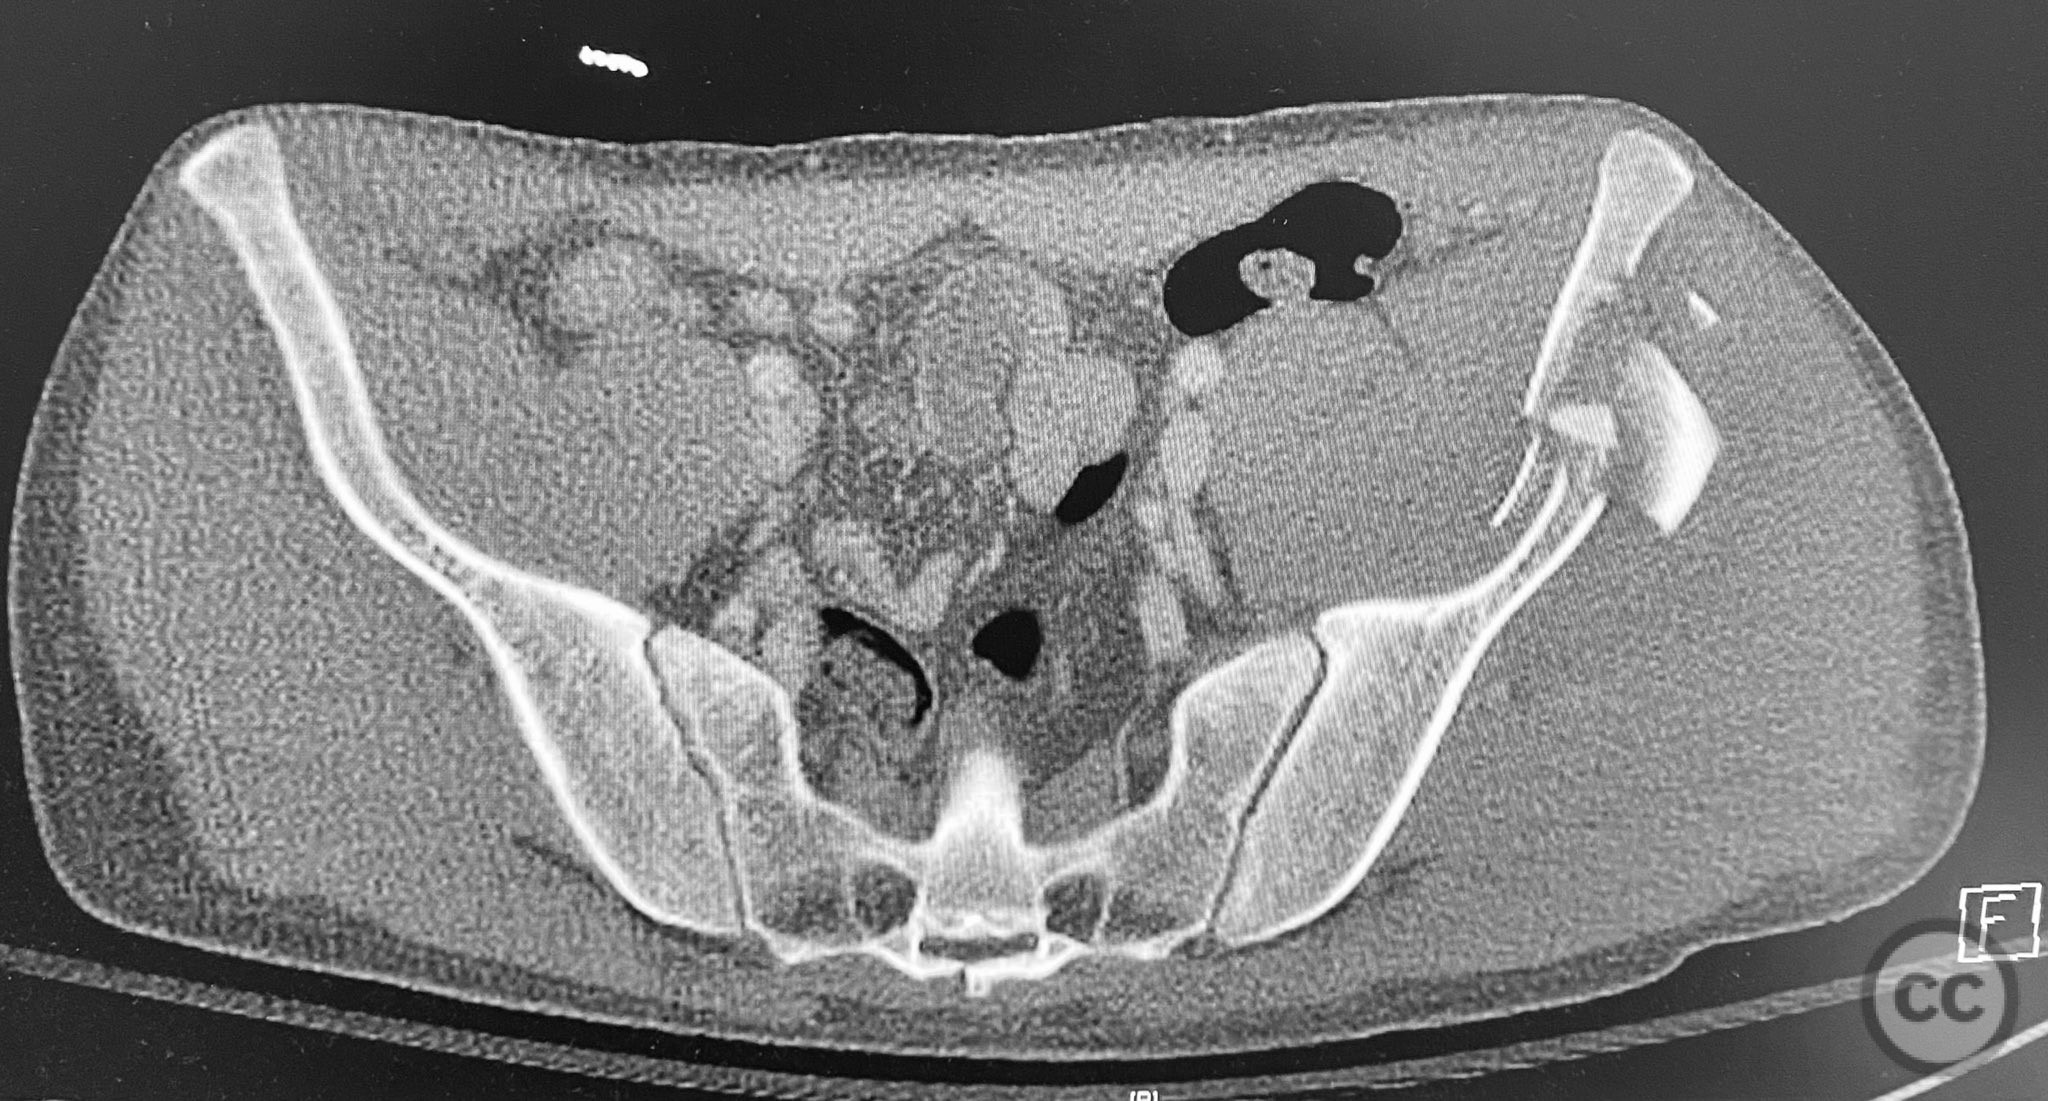

Clinical and radiological findings:  A patient sustained a high-energy injury resulting in an open, comminuted fracture of the iliac wing, sparing the pelvic ring. Associated injuries included spine, rib, and femur fractures. Initial radiographs and axial CT imaging demonstrated significant comminution of the iliac wing with intraosseous air densities indicative of an open wound. No pelvic ring disruption was identified. AO/OTA classification: 61-A2. The presence of multiple associated injuries is consistent with a direct lateral load mechanism.

Anatomical surgical approach:  A direct lateral approach to the os ilium was performed, with incision centered over the iliac crest. Subperiosteal dissection was carried down to expose the fractured segments of the ala ossis ilii. The open wound was incorporated into the exposure for thorough irrigation and debridement. Fracture fragments were anatomically reduced and stabilized with interfragmentary lag screws placed between the inner and outer tables of the ilium.